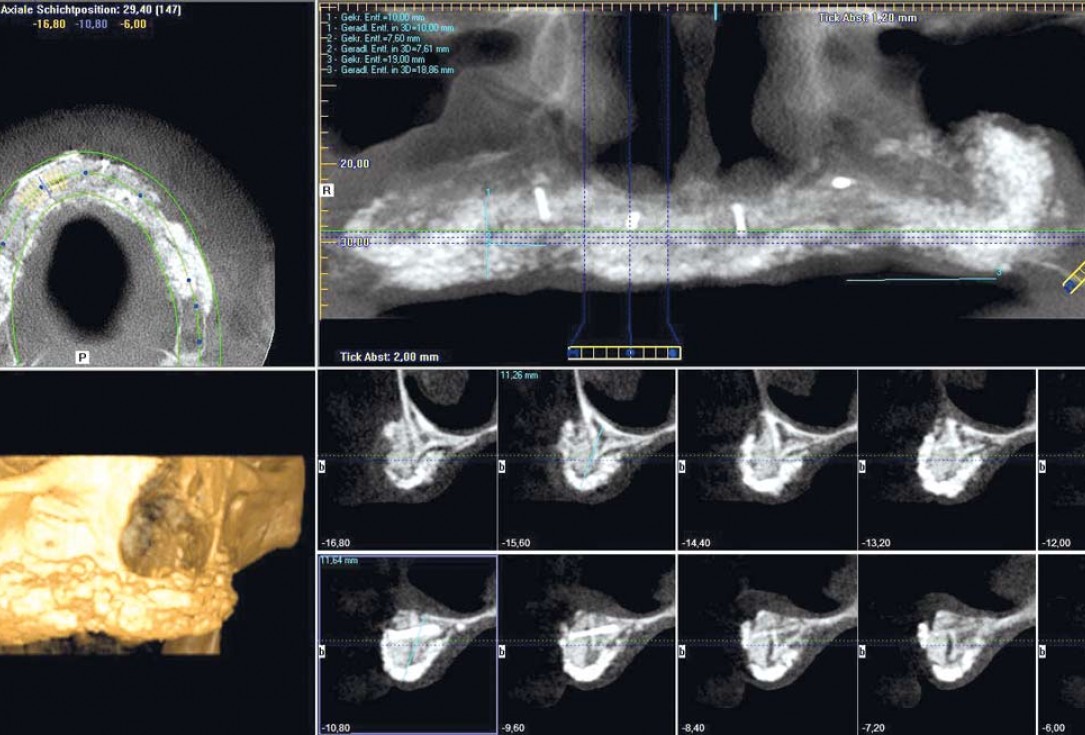

17/23 - Six months follow-up – stable situation

Full arch reconstruction of the maxilla with maxgraft® bonebuilder - Dr. M. Erbshäuser

18/23 - Six months follow-up – stable situation